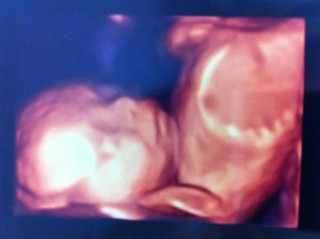

二人目です。体重は468gで順調のようです。今回どうやら爆睡中だったようで、口をへの字にして寝てるのがハッキリ写っていたのでとても愛らしくてたまりませんでした!胎動も元気いっぱいで長男と似た者兄弟になりそう‥(笑)楽しみです♪♪

初めて4Dで見た時の写真です。手を後ろに置いてニヤっと笑いながらとってもくつろいでたので、旦那と思わず笑ってしまいました。486gの男の子です!

推定体重450gです★

横顔と正面をバッチリ見せてくれ、すごくかわいい☆